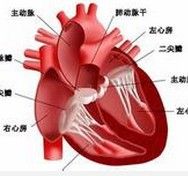

心衰 (二)根據心衰發生的部位可分為左心、右心和全心衰竭。左心衰竭的特徵是肺循環淤血;右心衰竭以體循環淤血為主要表現。

心衰的臨床表現與何側心室或心房受累有密切關係。左心衰竭的臨床特點主要是由於左心房和(或)右心室衰竭引起肺瘀血、肺水腫;而右心衰竭的臨床特點是由於右心房和(或)右心室衰竭引起體循環靜脈瘀血和水鈉瀦留。在發生左心衰竭後,右心也常相繼發生功能損害,最終導致全心衰竭。出現右心衰竭時,左心衰竭症狀可有所減輕。

心衰 一、基本病因引起心衰的原因很多,從病理生理基礎而言,主要是原發性心肌損害或心肌收縮期或舒張期負荷過重導致心肌細胞數量減少和心室舒縮功能低下的結果。

一、血流動力學異常任何原因引起的心衰,其基本問題是心室功能曲線低下,向右下方移位。即在任何特定的左室舒張末期壓時,心搏量較正常人為低。心室功能曲線反映心排血量與心室充盈壓之間的關係。根據Frank-Starling定律,隨著心室充盈壓的增高與舒張末期心肌纖維長度的增加,心搏量可相應增加,表現為心室功能曲線的上升。但這種心搏量的增加是有一定限度的,當左室舒張末期壓達2.0~2.4kPa(15~18mmHg)時,Frank-Starling機制達最大效應,此時心搏量不再增加,甚至反而降低,即為心室功能曲線的平台期和其後的下降。當心臟指數<2.2L/min·m2時,即出現低心排血量的症狀和體徵。左心室舒張末期壓增高將繼而引起左房壓、肺靜脈壓和肺毛細血管楔嵌壓的升高。當後者超過2.4kPa(18mmHg)時,即出現肺循環淤血的症狀和體徵。當右室舒張末期壓和右房壓升高致中心靜脈壓>1.6kPa(12mmHg)時,即出現體循環淤血征。隨著心排血量的減少和動脈血液的充盈不足,激活了各種神經內分泌的調節機制,特別是交感神經的激活,使外周循環阻力增加,外周血液重新分配,腎和骨骼肌血流減少,導致終末器官(endorgan)的異常。因此,充血性心衰時血流動力學異常的特點是:中心泵功能減退(心排血量降低,心室舒張末期壓增高);外周循環阻力增高和終末器官異常。

三、心肌損害和心室重構(remodeling)原發性心肌損害和心臟負荷過重使室壁應力增加,導致心室反應性肥大和擴大,心肌細胞和細胞外基質-膠原網的組成均有變化,這就是心室重構的過程。肥厚的心肌收縮速度下降;收縮時間延長;鬆弛延緩,但肌纖維縮短能力和心室排空能力並不減弱。因此如果心肌有適當的肥厚而足以克服室壁應力時,心室功能仍得以維持,臨床上亦不產生充血性心衰的症狀。因而,心肌肥厚在初期可起有益的代償作用。肥厚心臟如何發展至進行性心室擴大和心衰,其中機制尚不十分明了,能量耗竭可能是主要因素之一。由於肥厚心肌處於能量飢餓狀態,心肌缺血,心肌細胞死亡,繼以纖維化,剩下的存活心肌負荷進一步加重,心肌進一步肥厚伴進行性纖維化,如此形成惡性循環。當心肌肥厚不足以克服室壁應力時,左室進行性擴大伴功能減退,最後發展至不可逆性心肌損害的終末階段。上述三者之間是互相關聯,互為因果的。血流動力學異常可激活神經內分泌,加重心肌損害;神經內分泌的持續激活可直接損害心肌和加劇血流動力學異常;而心肌損害、左室進行性擴大和衰竭的結果又導致血流動力學紊亂的加重和神經內分泌的激活。